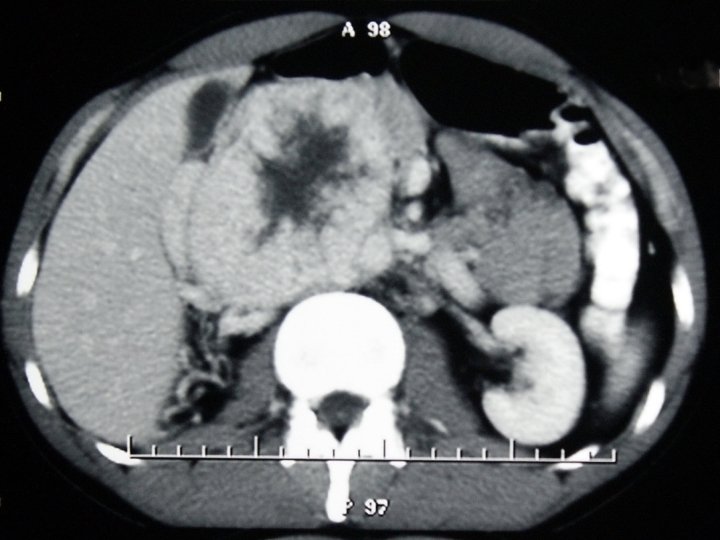

A 32 YO man presented because of fullness in his abdomen. The patient was an active young man without any complaint. Laboratory evaluation was negative.

Gene study done at Oxford University, UK showed that the patient does not have any mutation in NF 1, VHL, RET, SDH (A, B, C, D), SDHAF 2, TMEM 127, HIF 2 A and MAX genes.